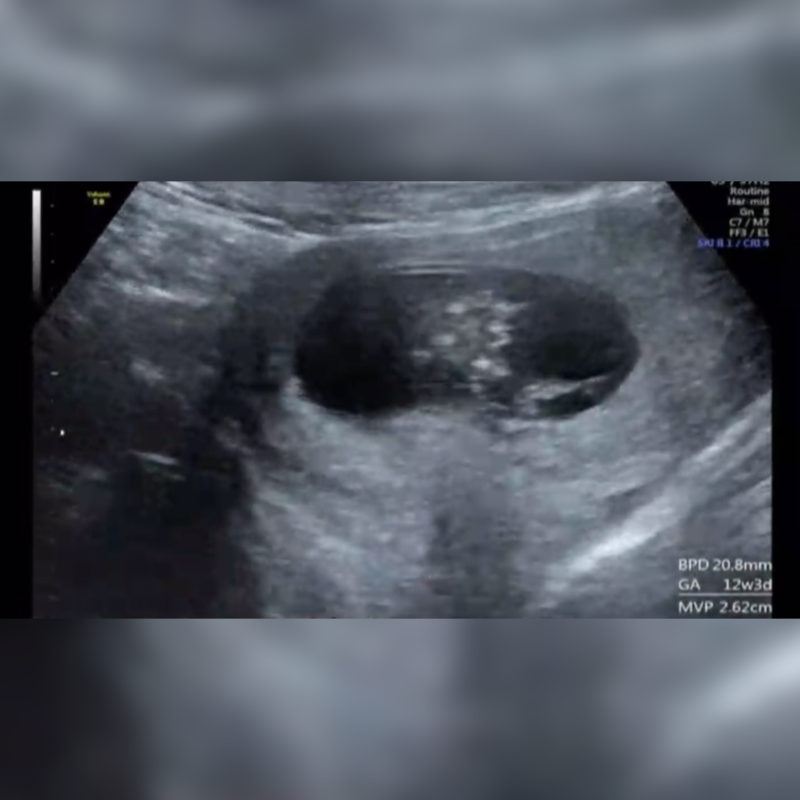

こんにちは! 12w4dのエコーなのですが、お股の間に突起物があるようにみえます。 男の子でしょうか? 女の子でも、このような突起物はありますか?